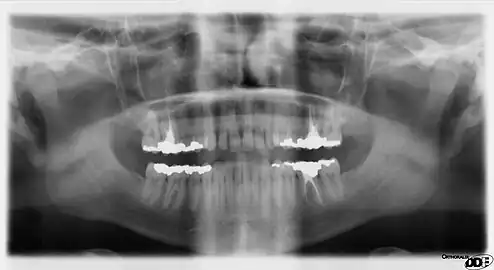

Panoramic radiograph

A dental panoramic radiograph, showing the maxilla and mandible, all the teeth including the "wisdom teeth," the frontal and maxillary sinuses, the nasal cavity and the temporomandibular joint and other near by head and neck anatomy.

A panoramic radiograph is a panoramic scanning dental X-ray of the upper and lower jaw. It shows a two-dimensional view of a half-circle from ear to ear. Panoramic radiography is a form of focal plane tomography; thus, images of multiple planes are taken to make up the composite panoramic image, where the maxilla and mandible are in the focal trough and the structures that are superficial and deep to the trough are blurred.